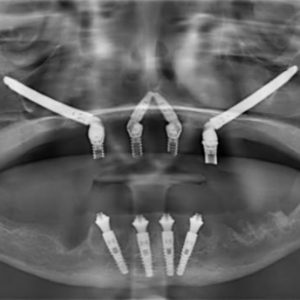

A implantodontia é um procedimento odontológico que envolve a colocação de implantes dentários de titânio no osso maxilar ou mandibular para substituir dentes perdidos. Os implantes proporcionam uma base sólida para a fixação de coroas, pontes ou próteses, restaurando a função mastigatória, estética e saúde bucal do paciente.